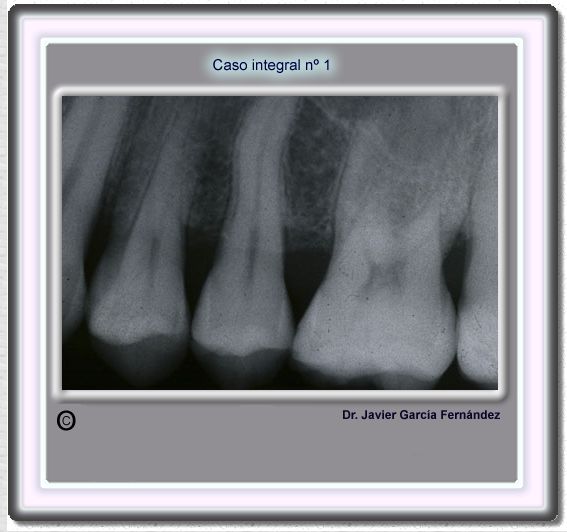

image 17